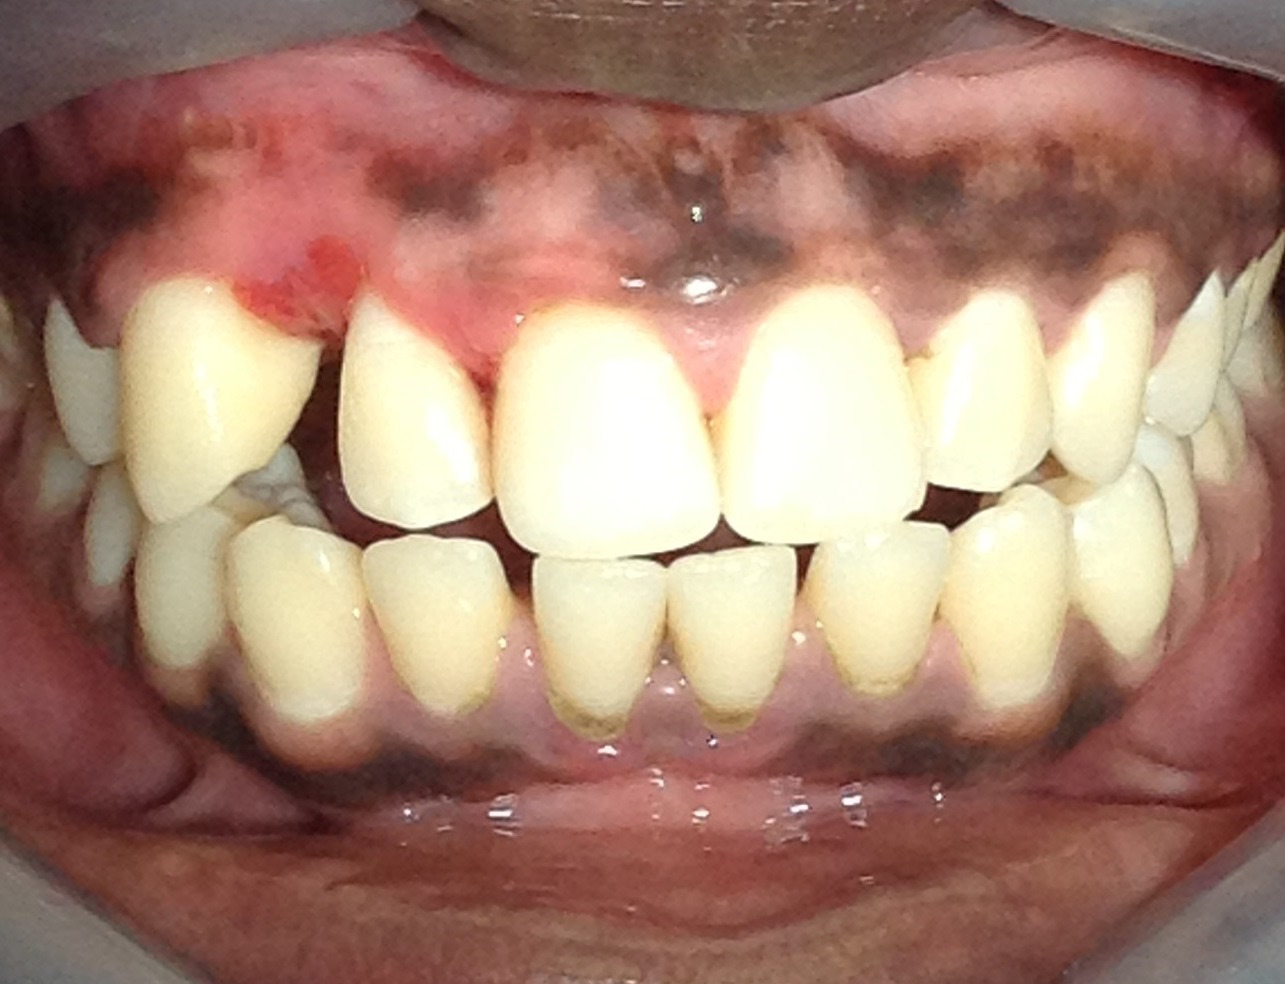

Melanin Pigmentation

Caused by increased melanin production in the oral mucosa

Melanin Pigmentation Location

gingiva and labial mucosa

Melanin Pigmentation appearance

flat, dark macule

borders well define or diffused

Melanin Pigmentation Demographic

in dark skin individuals

Melanin Pigmentation symptoms and tx

Asymptomatic. Biopsy if melanoma (cancer) is suspected